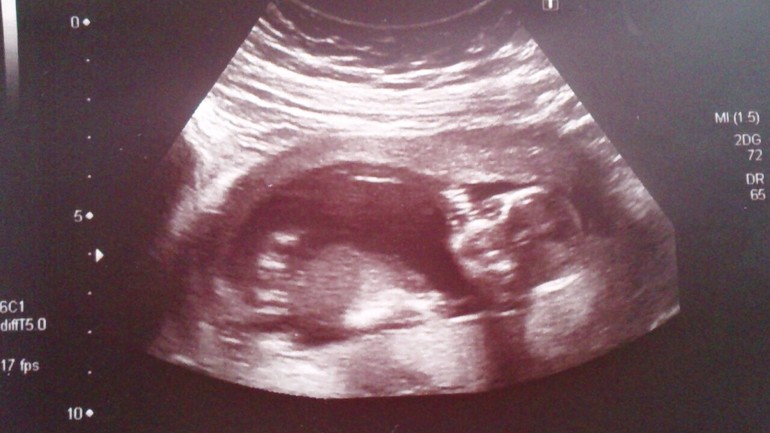

УЗИ 11,5 недель

КТР - 53мм, ТВП - 1,5мм, ЧСС - 160, ОГ - 68мм, ДБ - 6,5мм, носовая кость - 3мм.

Плацента по задней стенке.